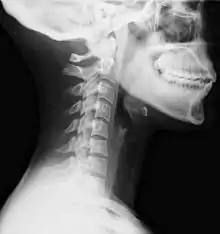

Lateral view X-ray of whiplash showing a loss of normal lordosis of the cervical vertebrae

Diagnosis occurs through a patient history, head and neck examination, X-rays to rule out bone fractures and may involve the use of medical imaging to determine if there are other injuries.[26]